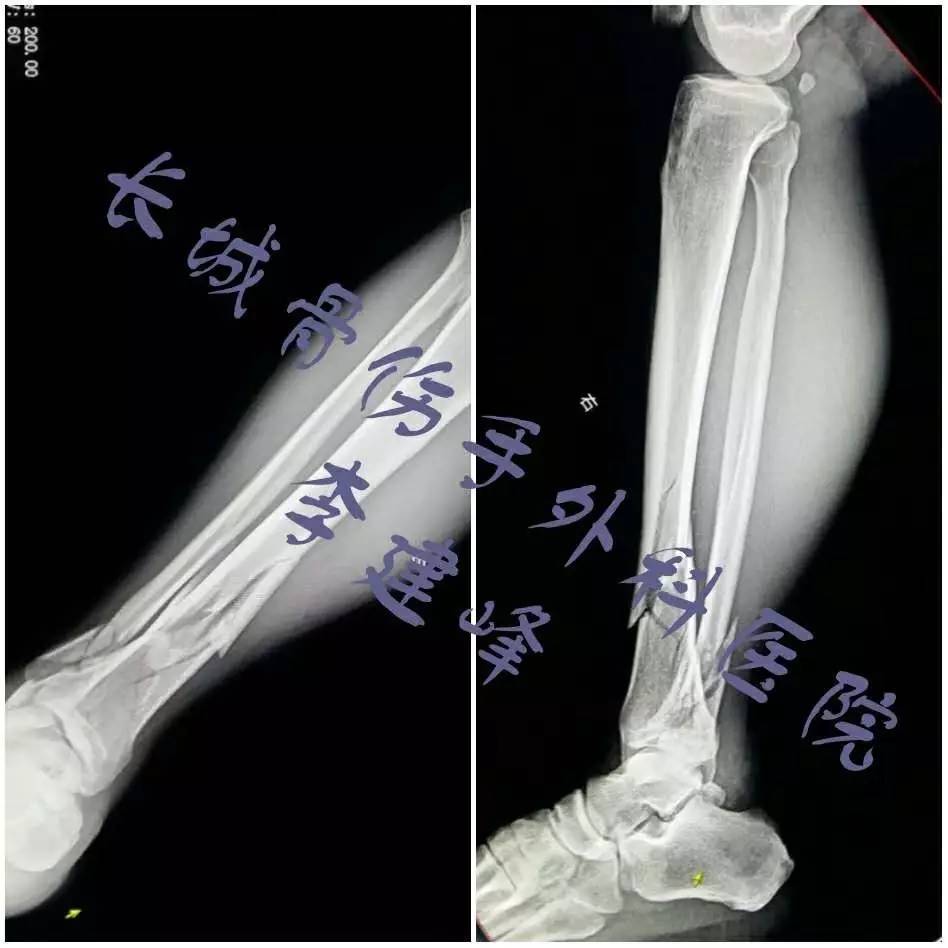

两例胫腓骨骨折治疗的选择 刻骨甘露 微信公众号文章阅读 Wemp